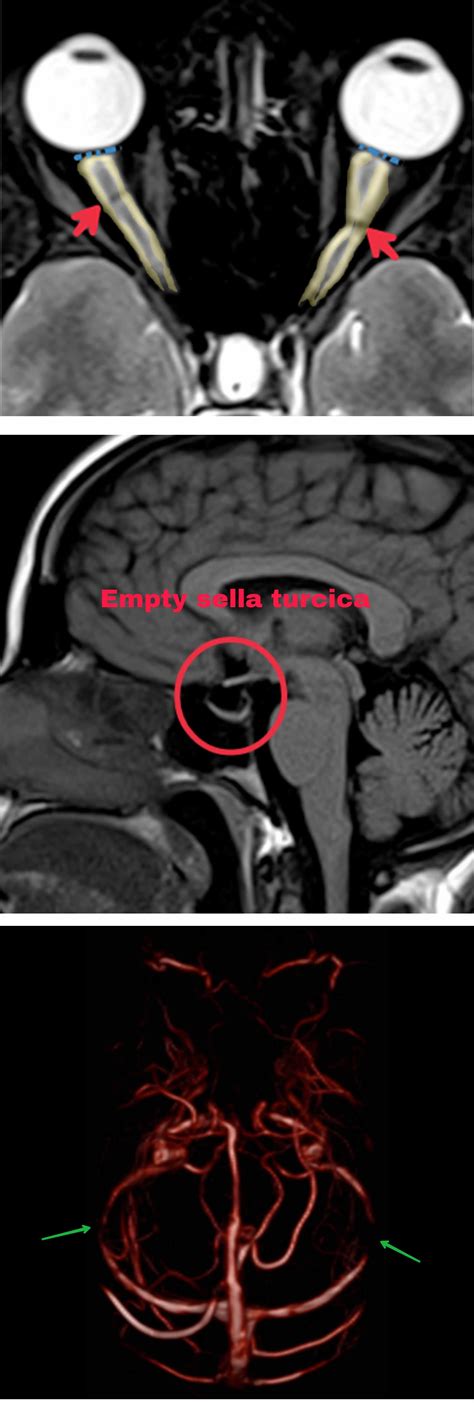

Diagnosing intracranial hypertension involves a combination of clinical evaluation, imaging studies, and diagnostic tests. Key diagnostic steps include:

• Imaging studies such as MRI or CT scans to rule out other causes of symptoms

• Lumbar puncture to measure cerebrospinal fluid (CSF) pressure and analyze CSF composition